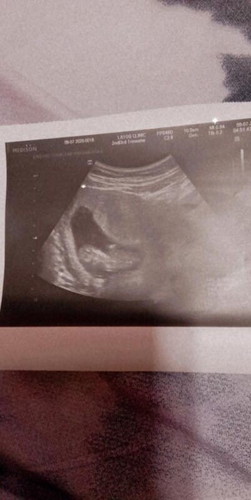

Hello po, I am 12 weeks and 2days pregnant. Is it normal lg po ba na maglight bleeding or spotting? Last Sept 7 I tried to have a check up sa ob ko po then okay namn po ang baby ko sa ultrasound 162 fetal heartbeat niya. And after that po ngbigay nang med si dok po pampakit for 1week. After ko po naubos ang med ngstop nadin light bleed ko then nung sunday po at ngayon bumalik na namn po. Aside from that wala namn po akong ibang complication na nararamdaman. #pregnancy #1stimemom #firstbaby